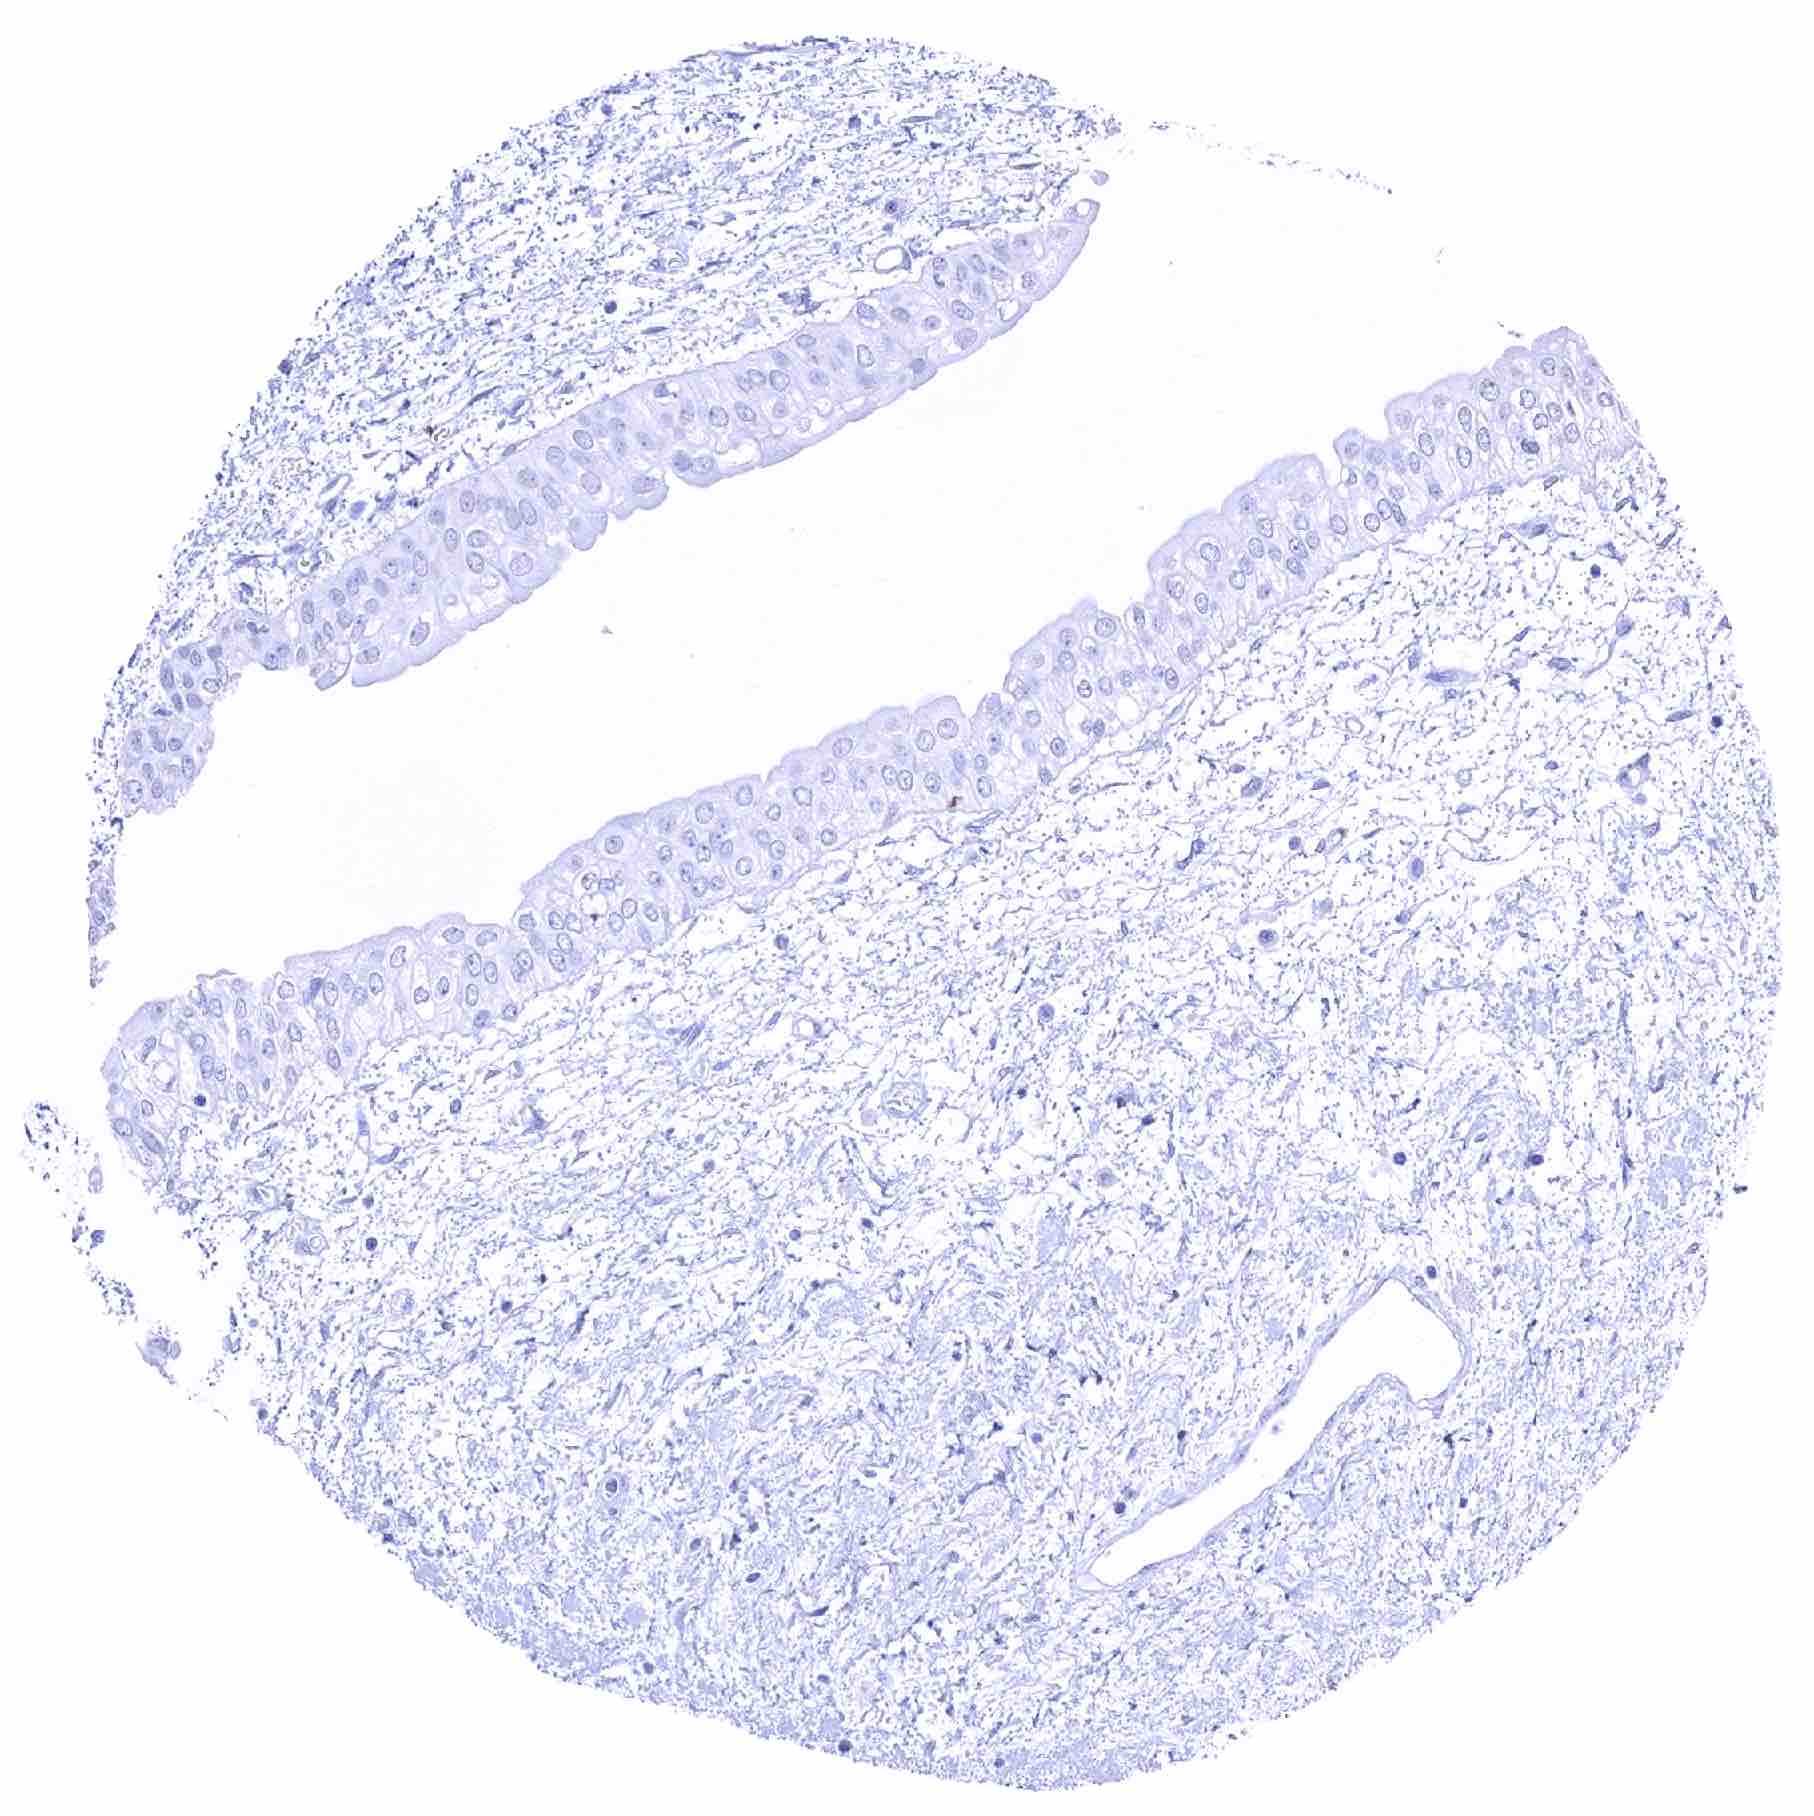

Uterus, endocervix – Endocervical cells are SOX2 negative in this sample

Uterus, endocervix – Weak to moderate SOX2 positivity of endocervical cells